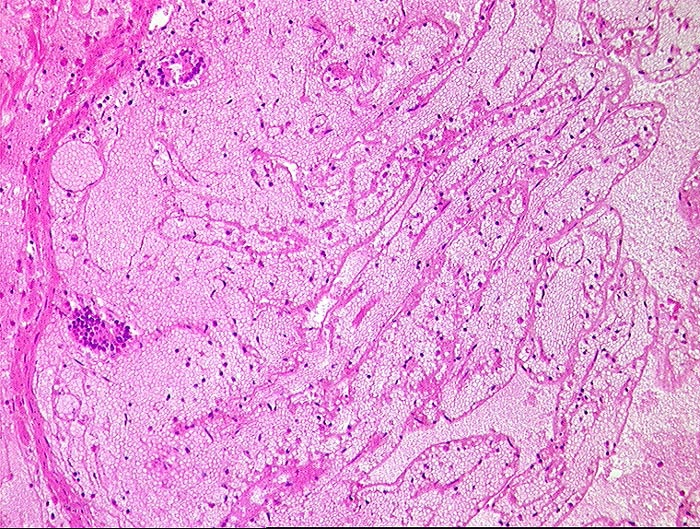

embolischer Mesenterialinfarkt

vaskulär / Durchblutungsstörung

Dünndarm

Hämorrhagische Nekrose der Mukosa.

Alter Myokardinfarkt Parietalthrombus. Frische Emboli in eröffneten Ästen der Arteria mesenterica superior.

Histologie